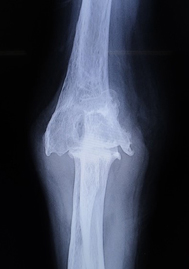

変形性関節症

非荷重関節である上肢の関節は腰や膝などと異なり変形する頻度は低いですが、高齢化に伴いその頻度は少しずつ増えています。またスポーツやいわゆる肉体労働をされる方においては若年であっても変形することがあります。変形性関節症に対する関節鏡手術、人工関節手術も積極的に行っています。とくに肘の関節鏡手術は手術侵襲が小さい割には術後の満足度は高く、慢性的な肘の痛みでお悩みの方は一度ご相談いただければと思います。